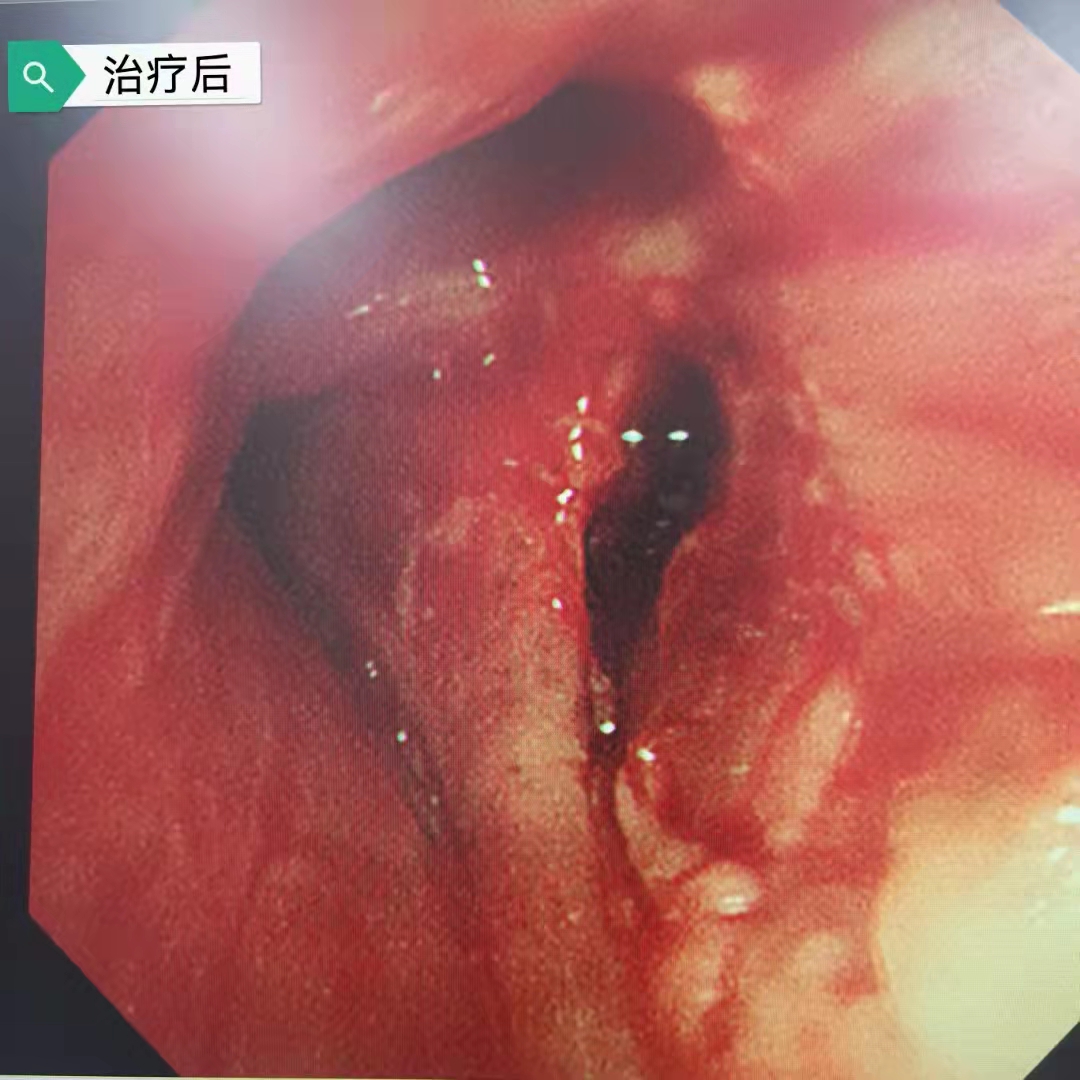

今日再次為一例肺部占位合并氣道內(nèi)腫瘤的患者施行支氣管鏡下的介入手術(shù),術(shù)前呼吸困難、心律失常二聯(lián)律,術(shù)后患者呼吸困難明顯緩解,且心律失常得以糾正,效果立竿見影。但是影像學(xué)的巨大腫塊,還需要結(jié)合病理分型采取恰當(dāng)?shù)木C合治療手段來減緩和控制疾病進(jìn)展。呼吸介入,我們團(tuán)隊一直在前進(jìn)中。